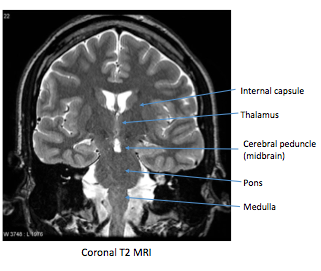

Label image shown

Top to bottom R to L:

Label the image shown

T2 weighted MRI:

On a T2 weighted MRI bone will appear black and CSF will appear white.

Note also that cerebral grey matter can be distinguished from white matter tracts on a T2 weighted MRI.